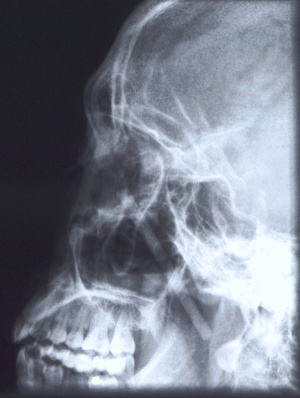

x-ray

Plain x-rays have a limited role in ophthalmic trauma in modern times. Historically it was the primary imaging of choice for the diagnosis of orbital and orbitofacial fractures. However, owing to the high degree of false negatives, and occasional false positives they are no longer utilized for that indication or in isolation. They are currently performed as a screening tool for radiopaque foreign bodies of the orbits and face. Prior to the advent of high-resolution CT scans, x-rays were used as a localizing tool prior to intervention for intraocular foreign bodies. This was achieved by obtaining images in various positions of gaze in which the foreign body could be seen moving within or against the planet of movement of the globe.

Computerized tomography (CT scan)

Computerized tomography is the imaging of choice for evaluating suspected orbital and orbitofacial fractures, intraorbital and intraocular foreign bodies and traumatic optic neuropathies. In the trauma setting, it is generally performed as a non-contrast study, with contrast indicated only in cases where there is concern for carotid-cavernous fistula. Axial images are useful in evaluation of the medial and lateral orbital walls, in addition to the medial and lateral rectus muscles. Coronal images are similarly useful in scrutinizing the superior and inferior orbital walls, the superior and inferior rectus muscles, and identifying optic nerve sheath hematoma. [29] While soft tissue window is useful for gross disruptions of the bone and soft tissue changes (EOM, Fat, Optic nerve, Brain, etc), Bone Windows are much more sensitive to detect orbital and orbitofacial fractures and should be viewed in the axial, coronal and sagittal views.

In the setting of orbital wall fracture, CT scan can often be helpful in demonstrating entrapped extraocular muscles. CT typically demonstrates linear floor fractures with minimal displacement and little or no soft tissue displacement in the maxillary antrum. However, associated soft tissue swelling, fat stranding, and muscular hematoma can often make radiographic interpretation difficult, especially in children where CT findings of entrapped extraocular tissues can be minimal. This emphasizes the importance of clinical exam using assessment of extraocular motility and forced ductions. Finally, CT can also be used o estimate the fracture area, which can be utilized as criterion for operative repair. [30]

In situations where a detailed clinical examination is not possible and there is a high suspicion of globe disruption, a CT scan may be indicated.[31] In patients with a clinical diagnosis of traumatic optic neuropathy, CT can be employed to asses for optic nerve canal fracture, foreign body, or bony impingment on the nerve.[32] It can also be employed for intraoperative navigation of the orbitofacial skeleton with 3-D modeling, in which images are acquired in the 0.6 – 1 mm formats. 3D reconstructions may be performed for patient education and treatment planning, which may be used for prebending orbital implants.

CT can also aid in the diagnosis of “open globe” injuries, defined as a full-thickness disruption of the sclera or cornea of the eye. Findings suggestive of an open globe injury on CT include a disruption of the globe contour, change in globe volume, variation in anterior chamber depth, and finally intraocular air, blood or foreign body. In one study, the sensitivity and specificity of detecting open globe injuries with CT was estimated at 75% and 93%, respectively. Therefore, although useful in the evaluation of traumatic injury to the globe, CT should not be relied upon solely for the assessment of open globe injuries. [29] Finally, CT scans of the orbits and face and not infrequently to assess completeness and accuracy of orbital reconstruction following fracture repairs, especially when postoperative complicaitons such as strabismus, motility disorders or optic neuropathy.

Cone Beam CT scans (CBCTs) may be considered in special situations either as a screening tool for bony injuries or as a postoperative evaluative tool following orbitofacial trauma repair especially with radiopaque implants.